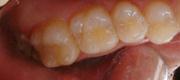

【ケース1】 メラニン(歯ぐきの黒ずみ)の除去例

【治療前】

【治療後】